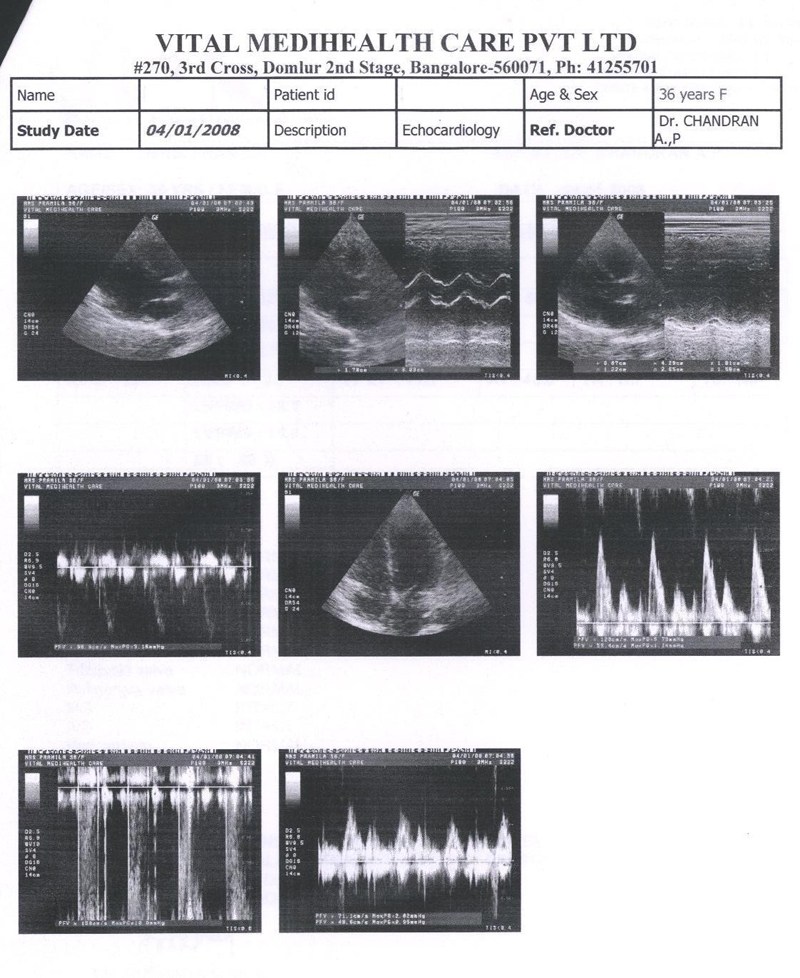

The Echocardiography done on 2nd Nov. 2006 done on Manipal Hospital clearly states Bicuspid and Thickened Aortic Valve, Mild Aortic Stenosis, Concentric LV Hyper trophy. But patient condition from 2nd Nov. to 2nd DEC had already deteriorated and she was supposed to be admitted in the Hospital By 15 th DEC. 2006

The Echocardiography report of 2nd Nov. 2006 is shown in fig 1

FIG 1:- Echocardiography report of 2nd Nov. 2006